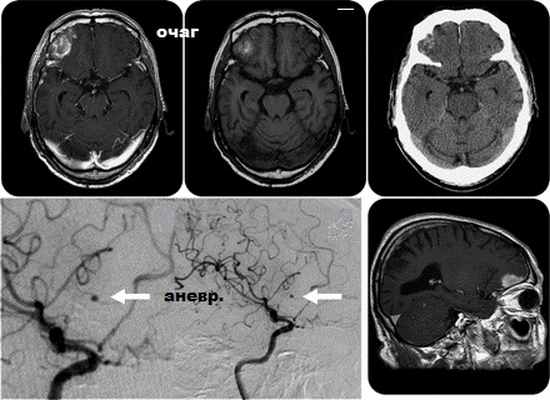

Нейровизуализация

При нейровизуализации головного мозга характерным является обнаружение корковых или корково-подкорковых инфарктов малых или средних размеров. Особенно подозрительны в отношении ПЭ инфаркты, расположенные в пределах разных сосудистых бассейнов – каротидных и/или вертебрально-базилярном. Наряду с «острыми» очагами ишемии возможно наличие «немых» инфарктов мозга.

Возникает на фоне повышения АД особенно при наличии аневризм (расширений) внутримозговых сосудов. Предрасположенность к этому осложнению можно выяснить при опросе врача и по МРТ головного мозга в сосудистом режиме.

![]()